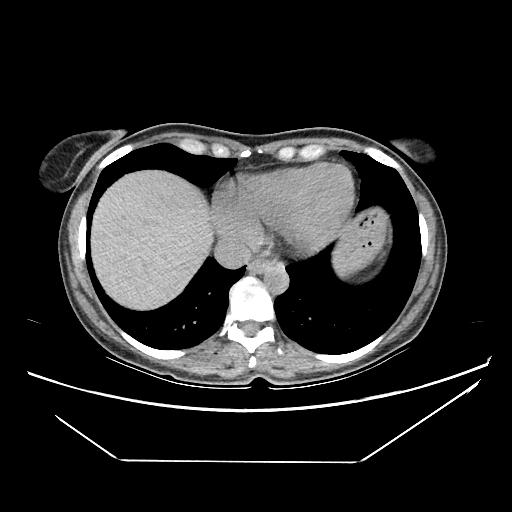

Original NATIVE CT scan (input)

Full window (WL 1023.5, WW 4095 β†’ Low βˆ’1024, High +3071)

Original VENOUS CT scan